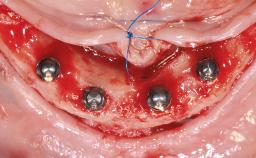

Conventional Loading of Four Implants in the Edentulous Maxilla and Restoration with a Bar-Supported Overdenture

A 64-year-old male patient was referred to the University Medical Center Groningen, The Netherlands, for dental implant treatment. The patient had been edentulous in both the maxilla and mandible for 25 years. During these 25 years, three conventional dentures had been fabricated, the most recent one being 2 years old. The patient complained of inadequate retention and stability of his maxillary and mandibular dentures. The esthetic aspect was of medium importance to the patient. His medical history was unremarkable.